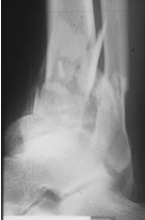

70jähriger Patient mit Pilontrümmerfraktur

offene Reposition über kleinem Zugang,

Minimalosteosynthese, gelenküberbrückender Hoffmann© II Fixateur.